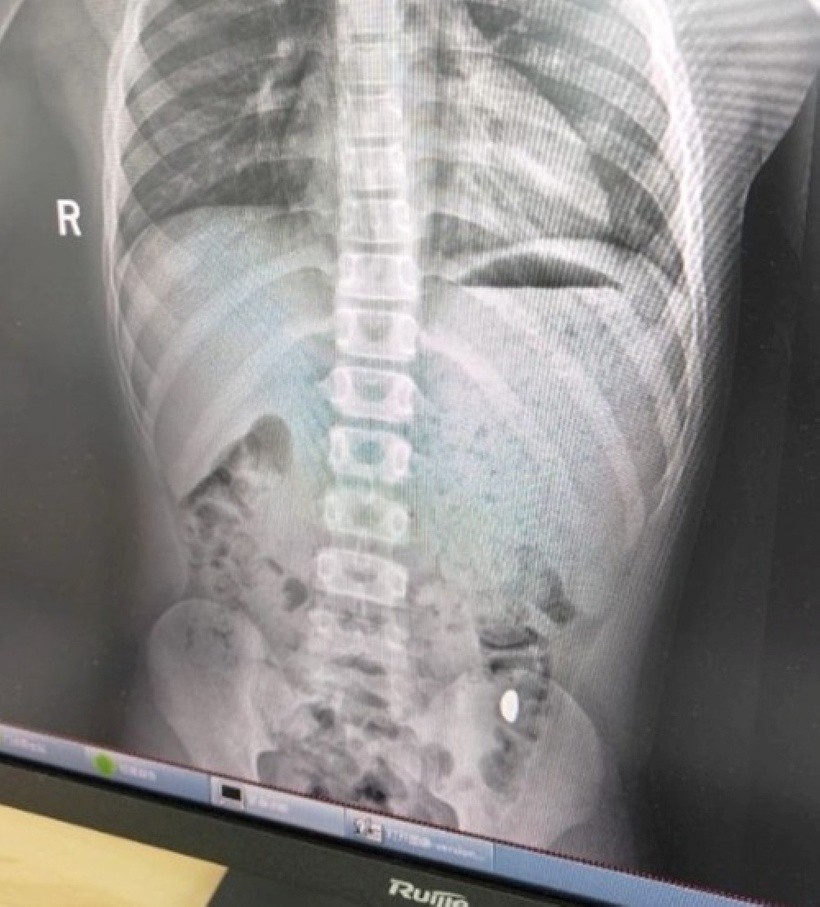

Kết quả chụp chiếu cho thấy có “vật thể lạ trong dạ dày”, nhưng cậu bé không có dấu hiệu đau bụng hay nôn ói. Cùng ngày, các bác sĩ đã lấy được hạt vàng ra, hiện không rõ là bằng phương pháp tự nhiên hay can thiệp y tế, theo báo Dân việt.

“Vật thể lạ trong dạ dày” cậu bé. Ảnh: Baidu.